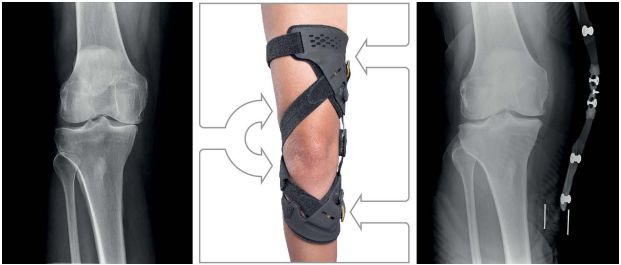

In einigen Fällen sind auch sehr aufwendige Orthesen indiziert, wie beispielsweise die speziellen Knie-Entlastungsorthesen. Hier wird durch ein innovatives Zugsystem das Körpergewicht von der schmerzhaften Gelenkregion umgeleitet in die weniger belastete Region. Anders ausgedrückt, es wird die mechanische Beinachse korrigiert, was zu einer Normalisierung der Belastungen der verschiedenen Gelenkregionen am Kniegelenk führt.

Auf der linken Seite sieht man das Röntgenbild vor Anwendung der Orthese mit einem vollständig aufgehobenen Gelenkspalt an der Knie-Innenseite, in der Mitte die anliegende Hochleistungs-Orthese und auf der rechten Seite, wieder im Röntgenbild, ist deutlich zu sehen, wie sich der Gelenkspalt sichtbar erweitert und es so rasch zu einer Schmerzreduktion kommt.